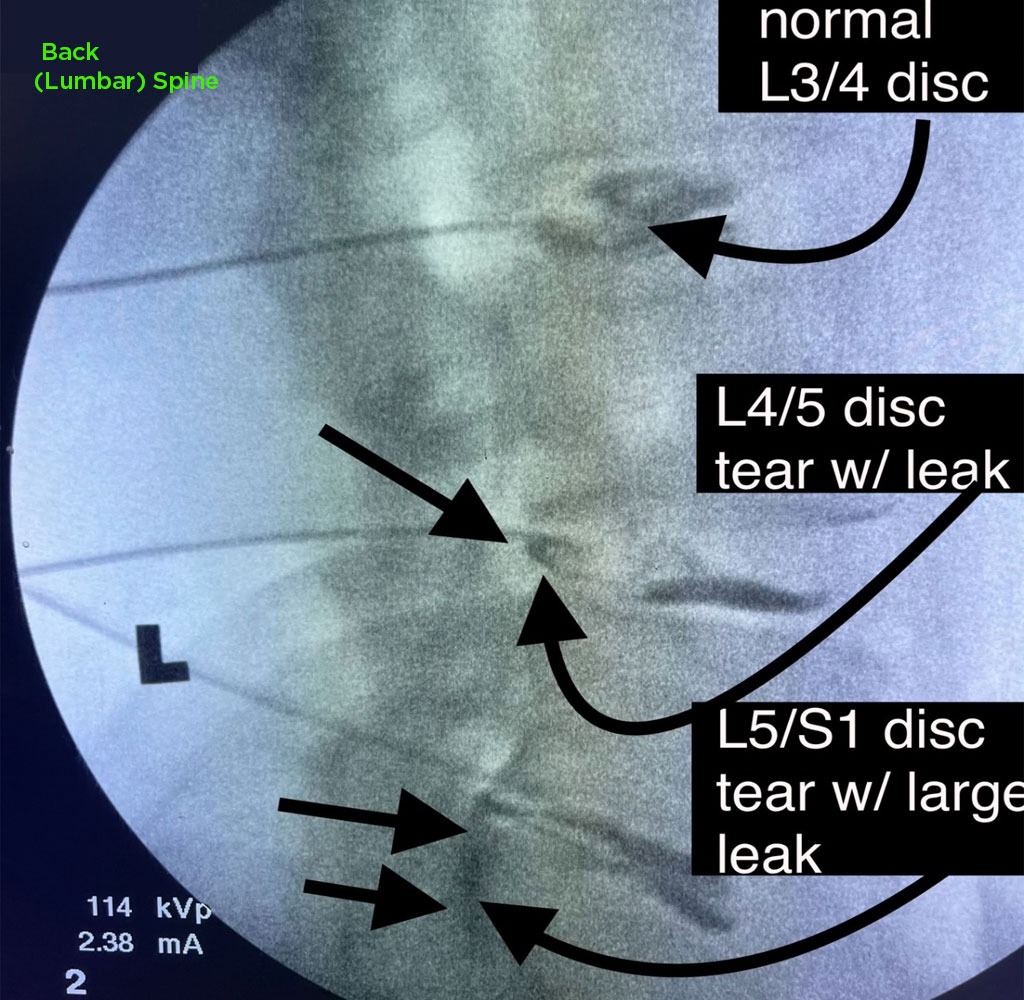

The Annulargram™ and MRI comparison

Figure 01: Comparison of Lumbar spine Annulargram™ and Lumbar spine MRI.

Tears in spinal discs cannot be seen on MRI nor discography. As shown: leaky discs are only visible on the Annulargram.